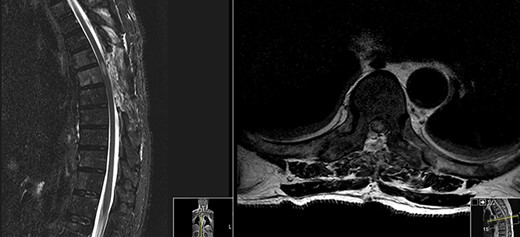

Postoperative MRI (Fig. 2) revealed a de novo T2 hyperintensity, possibly due to retraction of the thecal sac during surgery and consequently spinal cord lesion.

No hydrosyringomyelia or other complications were visible.